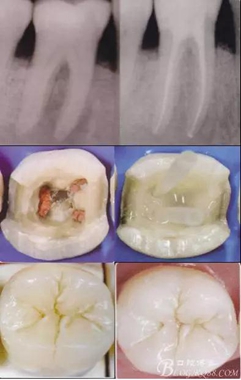

高嵌體粘固后X片

高嵌體病例圖片